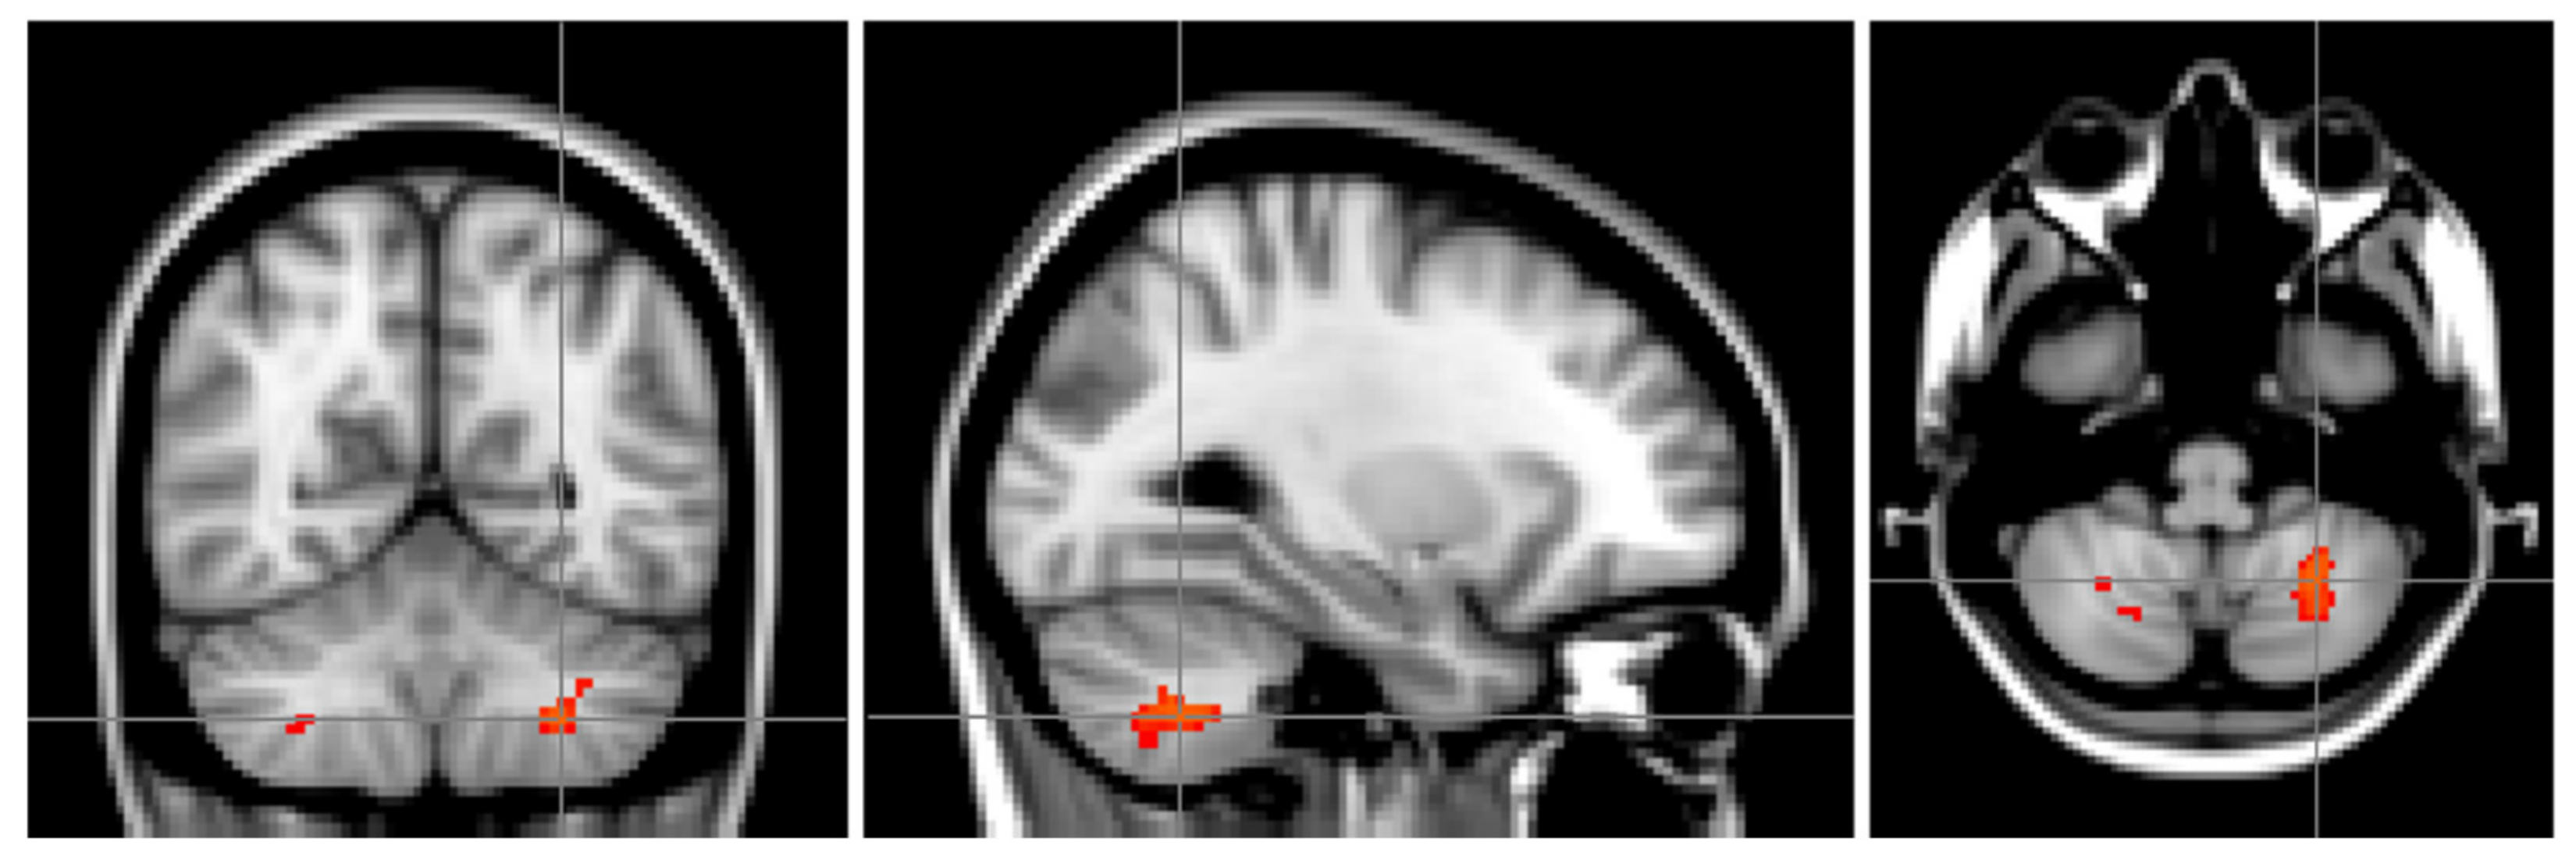

| 1 | 126 | 0.03 | −26 | −58 | −46 | −27.4 | −60.1 | −44.9 | 35% L. VIIIa, 5% L. VIIb |

| 2 | 52 | 0.04 | 38 | −48 | −52 | 38.5 | −50.8 | −51.5 | 65% R. VIIIa, 30% R. VIIb, 4% R. Crus II |

| 3 | 12 | 0.05 | 16 | −66 | −42 | 17.8 | −65.7 | −43 | 21% R. VIIIa, 15% R. VIIb, 1% R. Crus II |

| 4 | 4 | 0.05 | 28 | −60 | −46 | 29.5 | −59.5 | −46.5 | 36% R. VIIIa, 16% R. VIIb, 1% R. VIIIb |

| 5 | 2 | 0.05 | 8 | −62 | −28 | 8 | −62 | −27 | 3% R. VI, 2% Vermis VI, 1% R. VIIIa, 1% R. V |